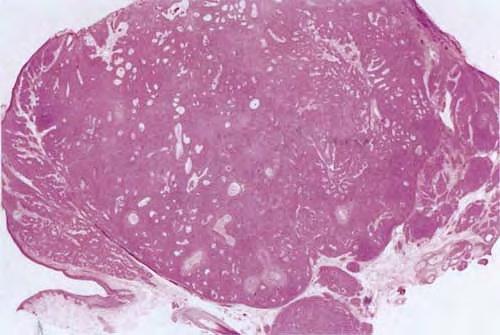

Hidroacanthoma simplex shows sharply demarcated aggregations of cuboid to ovoid cells confined to the epidermis. Eccrine poroma reveals aggregations of uniform basaloid cells that radiate from the basal layer of the epidermis into the dermis . Dermal duct tumor consists of several sharply circumscribed, mainly dermal nodules composed of poroid and cuticular cells. Ductal structures are frequently observed. Poroid hidradenoma is characterized by intradermal, solid, and cystic aggregations of poroid cells.